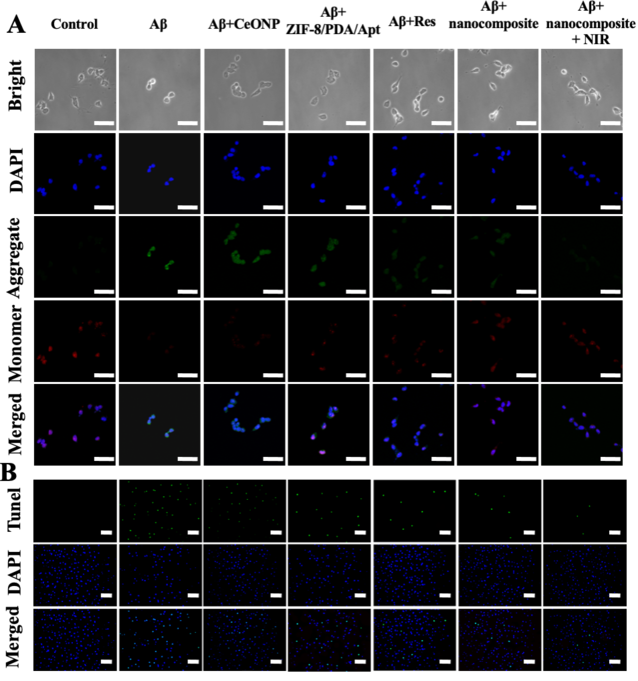

我們針對Aβ自聚集的現(xiàn)象,考察了該探針在抑制Aβ聚集以及解離原纖維方面的療效。ThT和TEM結(jié)果表明(圖四),探針既能夠抑制Aβ單體聚集,又能解聚Aβ原纖維,并且在光熱照射下,該性能能夠得到增強(qiáng)。細(xì)胞內(nèi)治療結(jié)果表明,該探針能夠在細(xì)胞水平,有效抑制Aβ單體聚集,清除AβO誘導(dǎo)的細(xì)胞內(nèi)過量ROS,并且探針的光熱性能,能夠增強(qiáng)其治療效果(圖五)。此外,JC-1、TUNEL以及Calcium-AM/PI染色結(jié)果均表明,該探針可以有效地保護(hù)神經(jīng)細(xì)胞免于Aβ誘導(dǎo)產(chǎn)生的凋亡。

【圖五】探針在細(xì)胞水平的治療效果考察